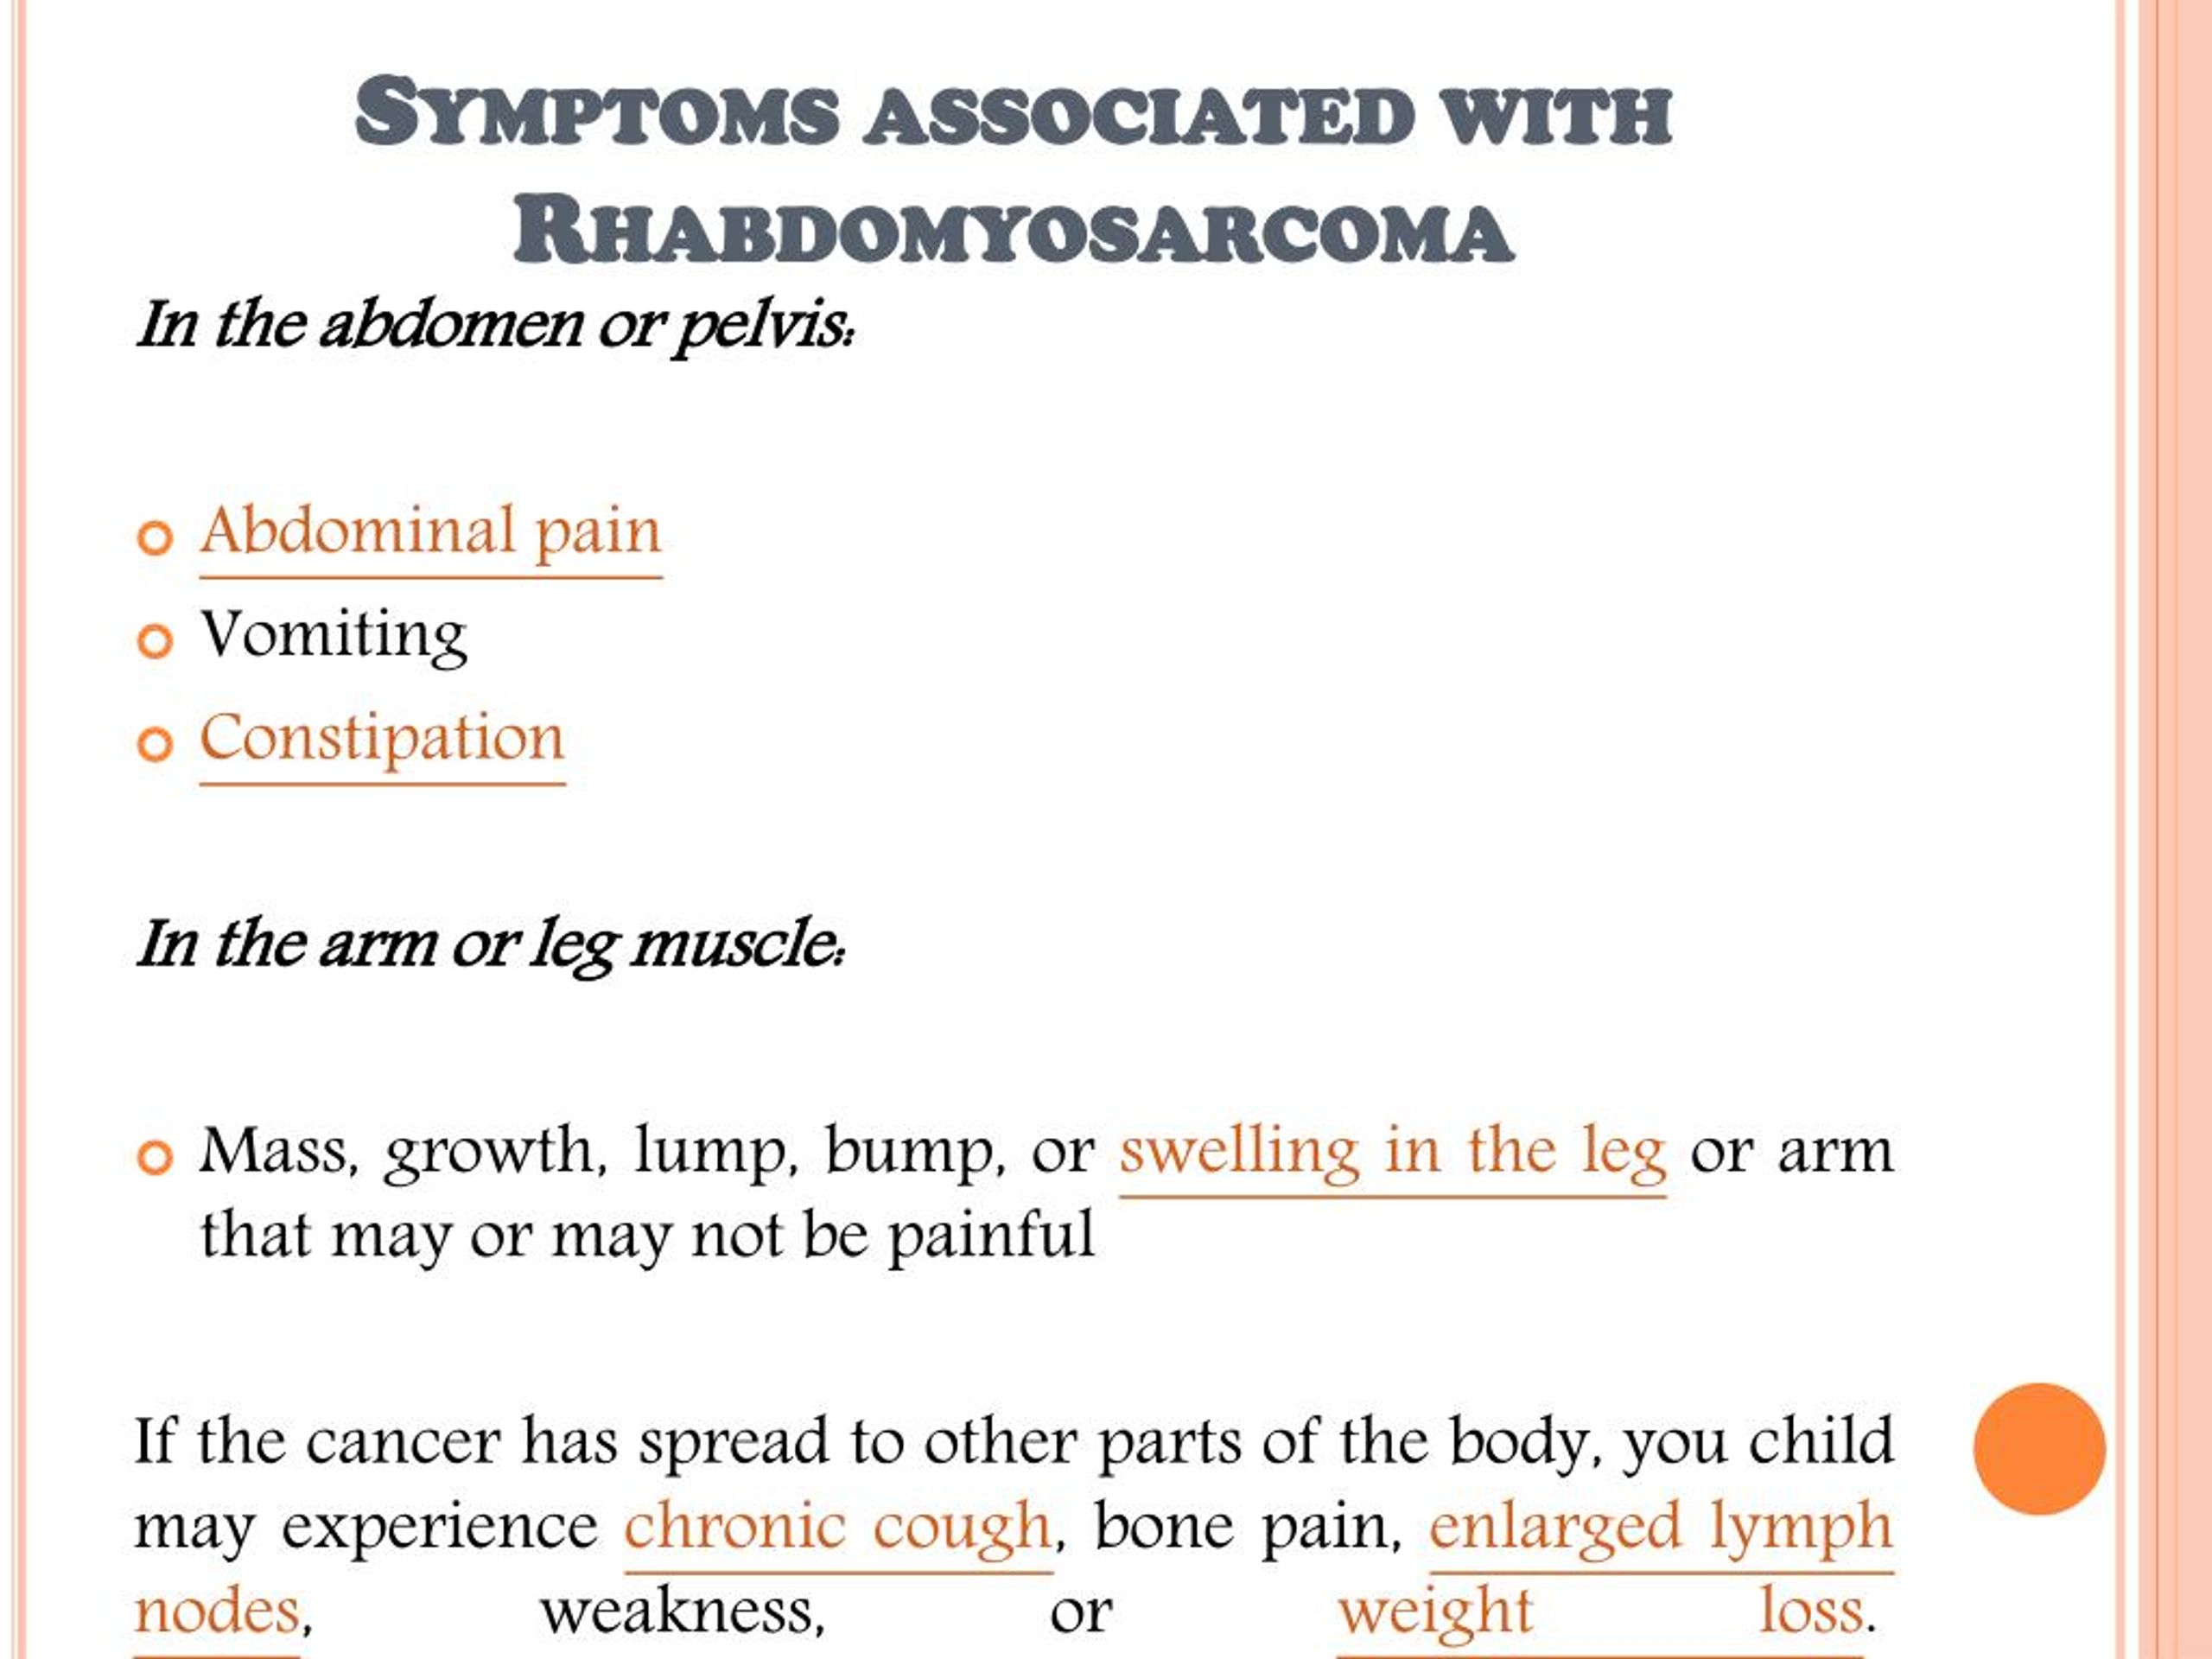

PPT - Rhabdomyosarcoma (RMS): Information On Symptoms, Diagnosis And

www.slideserve.com

www.slideserve.com

rhabdomyosarcoma symptoms treatment rms diagnosis information ppt powerpoint presentation

Rhabdomyosarcoma Symptoms And Causes - Apollo Hospitals Blog

healthlibrary.askapollo.com

healthlibrary.askapollo.com